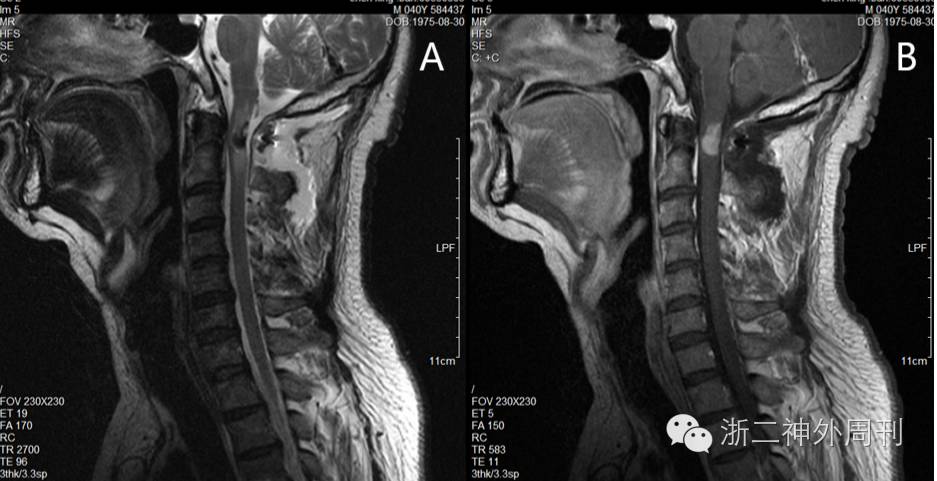

术后患者左上肢麻木减轻,无肢体肌力异常。查MRI显示肿瘤部分切除(图4)。

4. 术后T2加权相及增强相均提示肿瘤残留,但突出脊髓部分已切除。